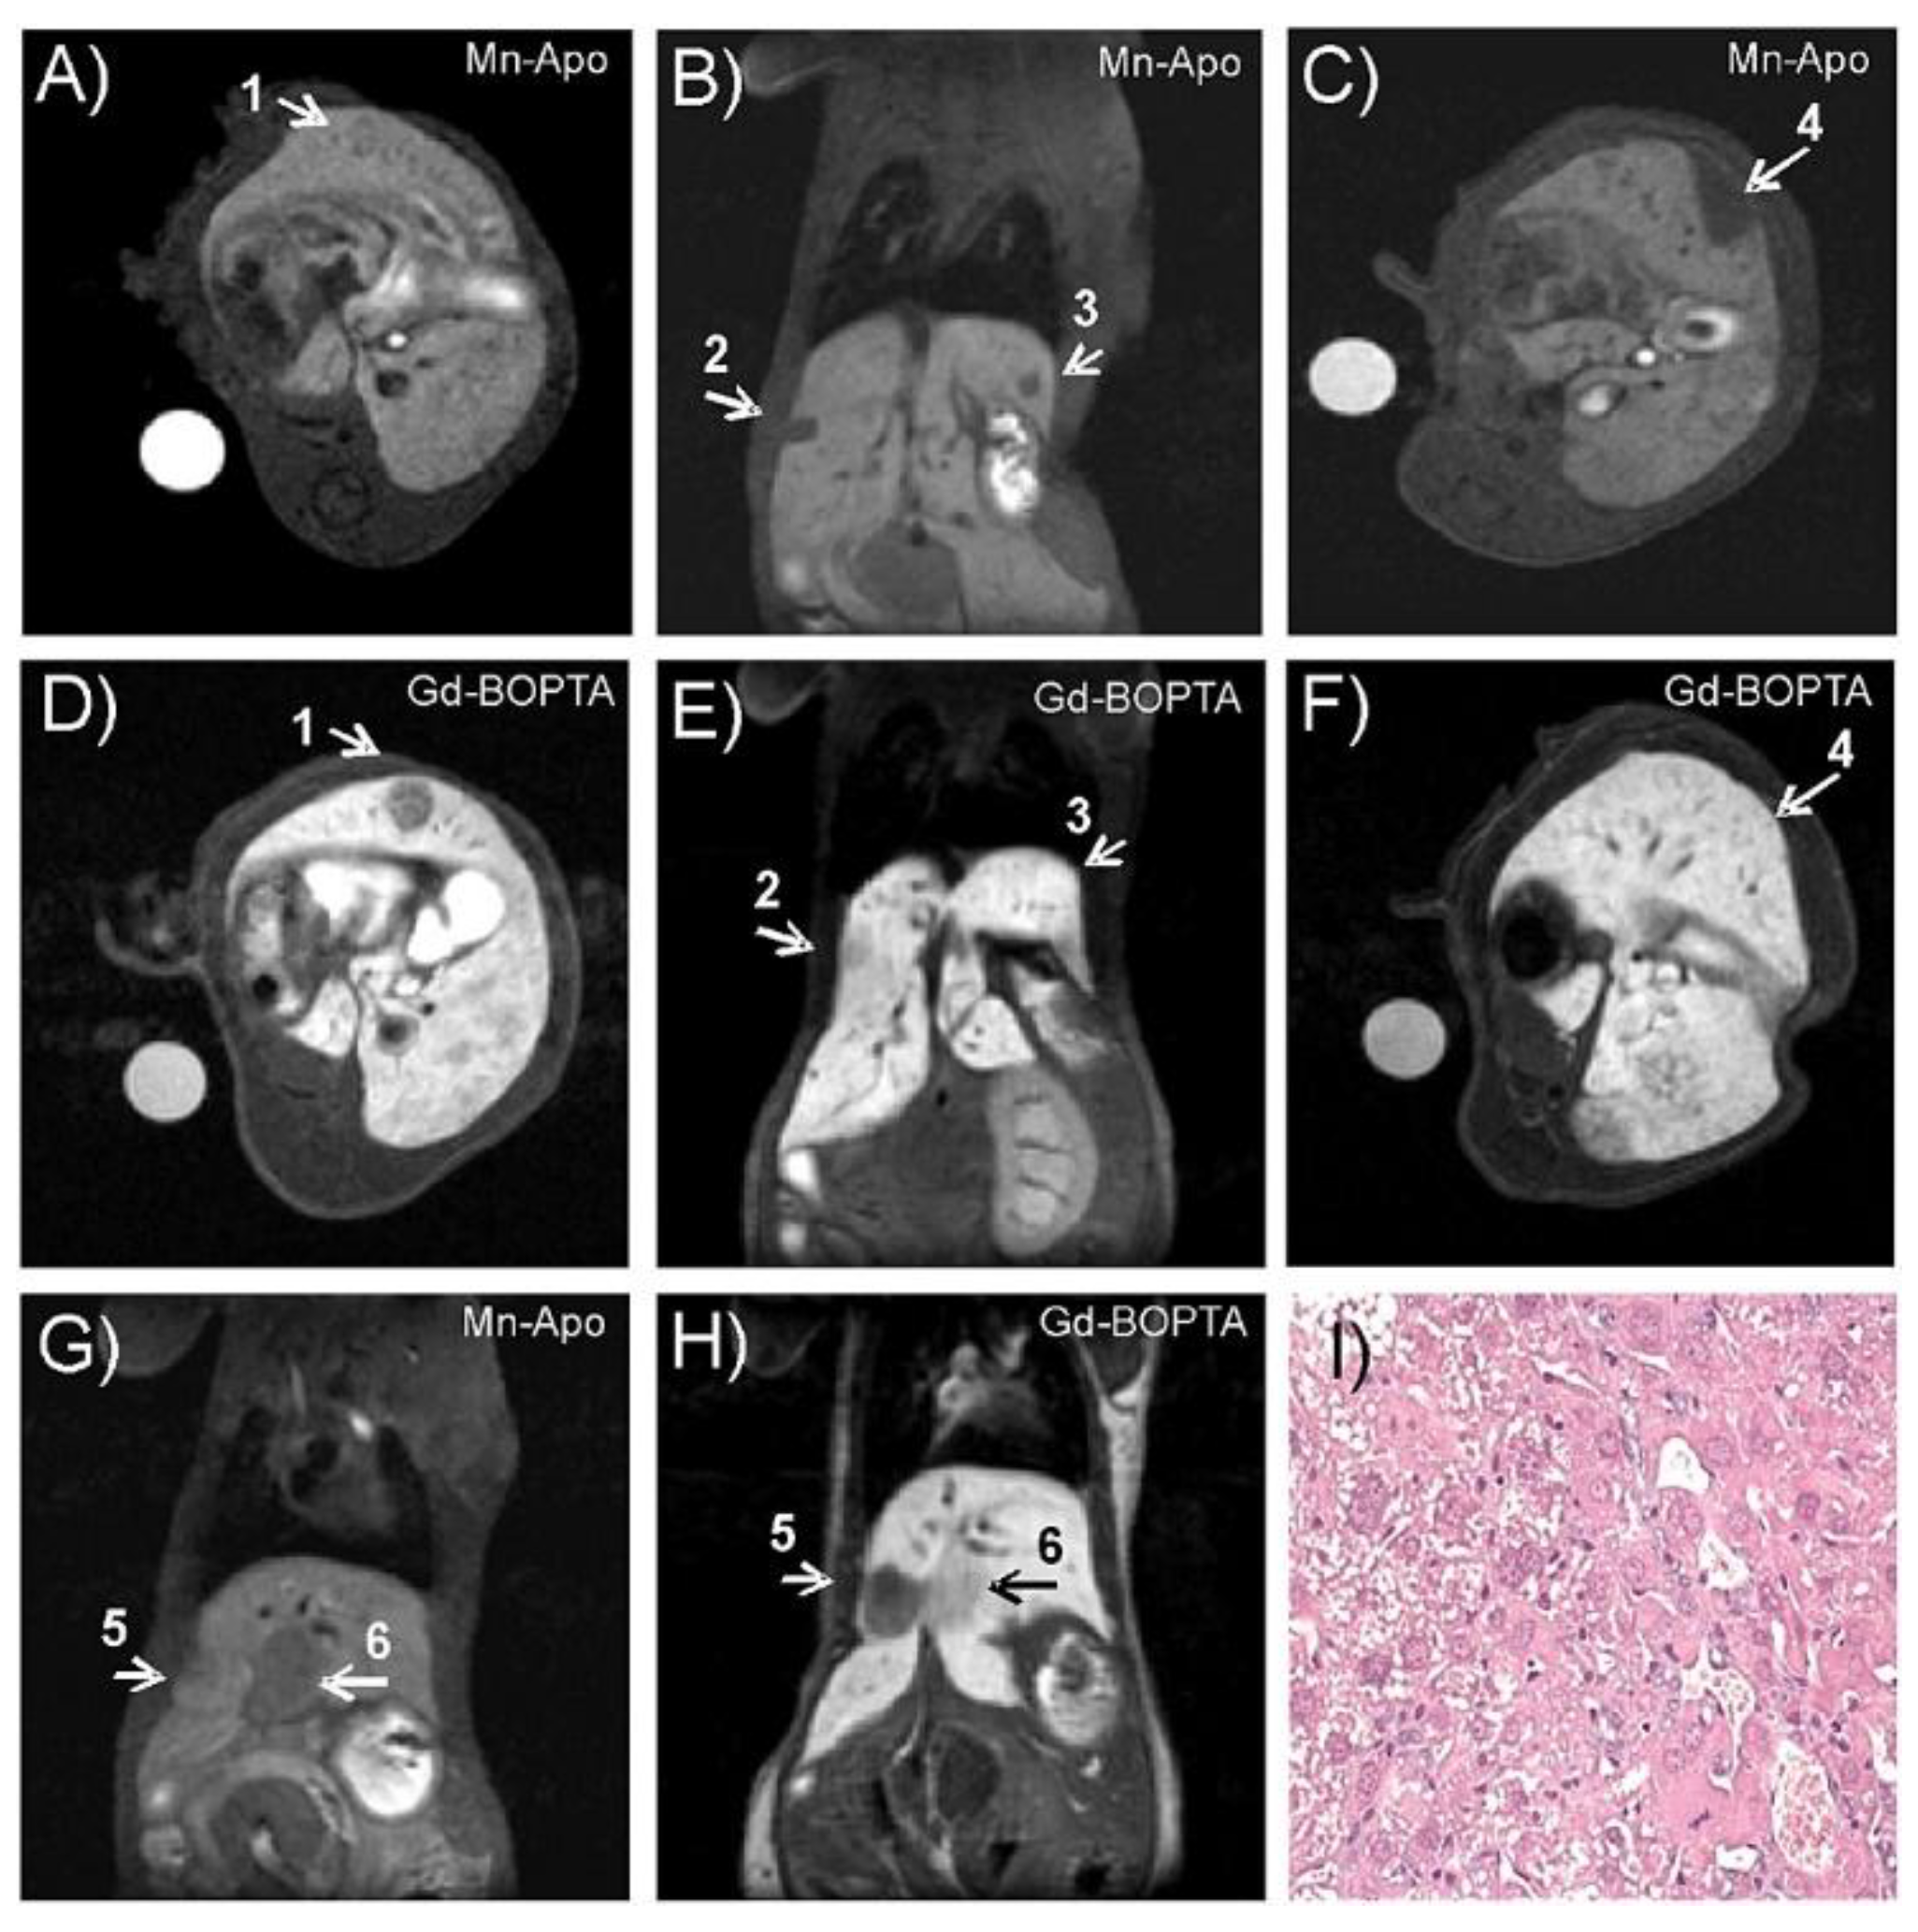

- Geninatti Crich, S.; Cutrin, J.C.; Lanzardo, S.; Conti, L.; Kálmán, F.K.; Szabó, I.; Lago, N.R.; Iolascon, A.; Aime, S. Mn-loaded apoferritin: A highly sensitive MRI imaging probe for the detection and characterization of hepatocarcinoma lesions in a transgenic mouse model. Contrast Media Mol. Imaging 2012, 7, 281–288. [Google Scholar] [CrossRef] [PubMed]

- Geninatti Crich, S.; Cadenazzi, M.; Lanzardo, S.; Conti, L.; Ruiu, R.; Alberti, D.; Cavallo, F.; Cutrin, J.C.; Aime, S. Targeting ferritin receptors for the selective delivery of imaging and therapeutic agents to breast cancer cells. Nanoscale 2015, 7, 6527–6533. [Google Scholar] [CrossRef] [PubMed]